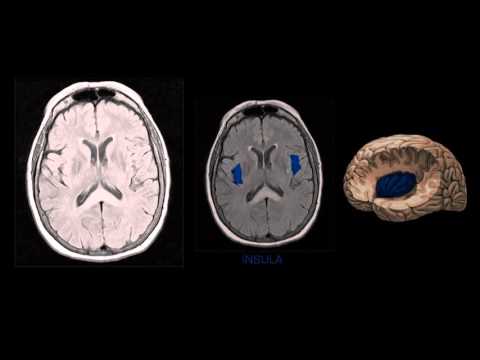

na flechinha reta a parte mais externa né que é formada por corpos e neurônios e na substância Branca formado por fibras essa setinha curva aqui dá pra gente ver a diferença que é bem nítida né na imagem aqui também a gente vê consegue visualizar os núcleos da base né mas isso aí vou falar mais na frente agora o uma divisão dos lobos né como é que a gente visualiza os lobos o frontal o temporal a ínsula o occipital e o parietal bom aqui eu destaquei em laranja o lobo frontal e em seguida uma marca importante

que é o suco lateral ou a fissura de silvios e ele é importante pra gente conseguir identificar e conseguir delimitar o que é lobo frontal do que é lobo temporal e de onde estaria por por exemplo o lobo da ínsula então aqui em verde eu destaquei o suco lateral ou fissura de silvios né em seguida o lobo temporal aqui em rosa essa parte para trás da fissura ou do suco de silvios o lobo ospital todo mundo já sabe aqui a gente vê o lobo em destacado em azul o lobo da ínsula que é um lobo

mais interno né dá para ver aqui nessa imagem à direita a última à direita colorida uma imagem do Netter com com o corte aqui na região temporal que dá para visualizar o lobo da ínsula eu não coloquei aqui as funções de cada um dos lobos eu vou deixar isso para um próximo vídeo eu vou colocar resumido o que cada Lobo corresponde a cada função vamos ver dá uma olhada nas estruturas né nas principais estruturas que podem ser visualizadas eu à medida do possível eu coloco sempre o corte sagital e o axial lado a lado pra